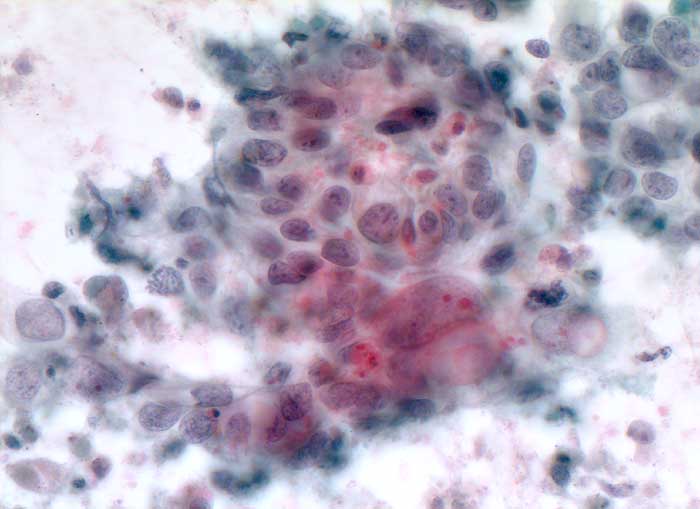

p/ Lebermetastase eines Adenokarzinoms (Magen)

Lebermetastase eines Adenokarzinoms (Magen)

Die Abgrenzung einer Metastase eines wenig differenzierten Adenokarzinoms von einem wenig differenzierten hepatozellulären Karzinom kann schwierig sein. Als wichtige Kriterien für ein HCC gelten monomorphe polygonale Zellen mit zentralen Kernen, Kapillarendothelien und Einschlüsse von Gallepigment. Zur Klärung der Herkunft des Primärtumors können immunzytochemische Untersuchungen weiterhelfen.